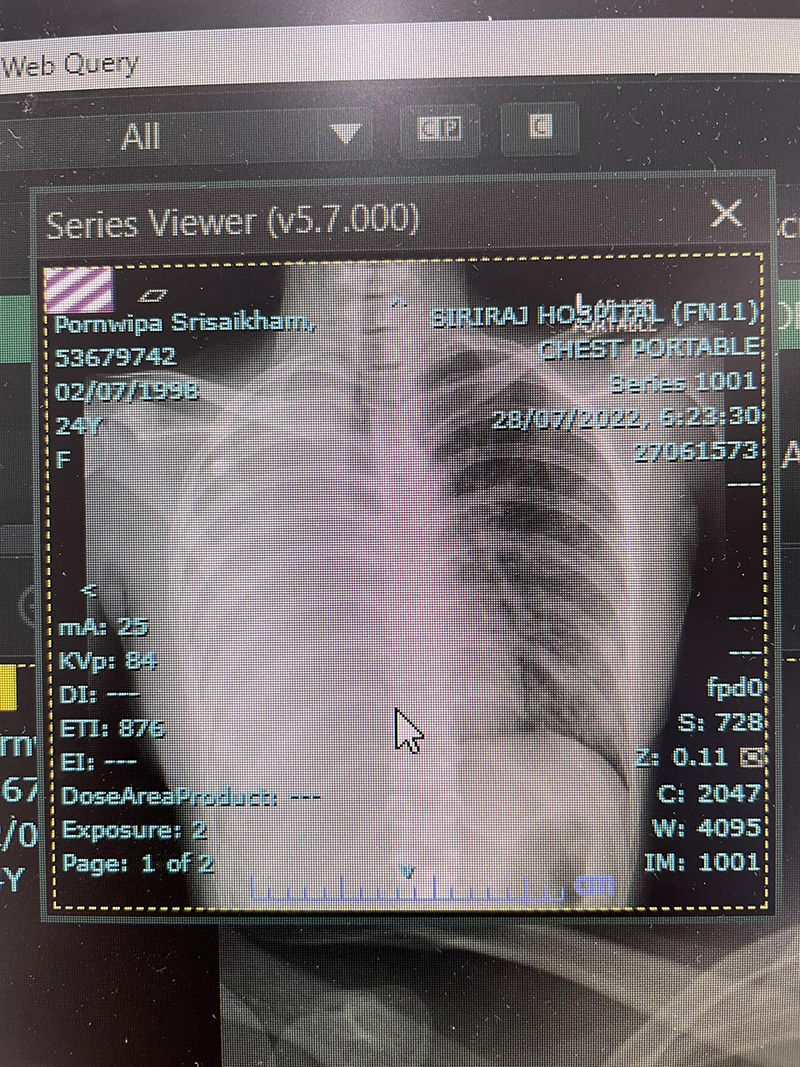

พี่ที่รู้จัก (คนดีคนเดิม) นัดคิวตรวจอายุรศาสตร์ให้ ไปตรวจอายุรศาสตร์ครั้งแรก เจาะเลือด x-ray แบบชุดใหญ่ไฟกะพริบ ผล x-ray ก็ยังคงปกติ แต่ผลเลือดค่าตับไม่ค่อยดี แต่หมอไม่ว่าไง ยังคงมีอาการไออยู่ หมอจึงพาไปให้หมอเฉพาะทางด้านปอดดู หมอปอด ส่งตรวจ CT Chest ผลเจอก้อนที่ปอด (หลายก้อน ใหญ่สุด 4 cm) และที่ตับ 2 ก้อน จึงนัดตัดชิ้นเนื้อไปตรวจ